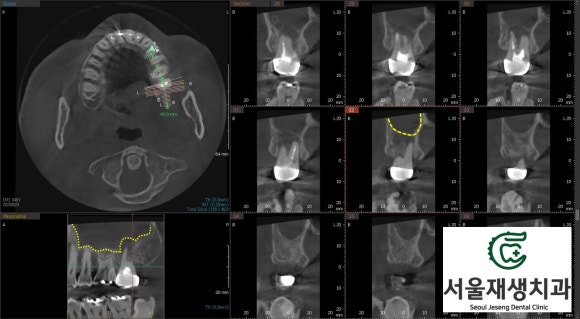

윗 어금니에 발생한 염증은 상악동(부비동의 하나, 광대뼈 하방에 존재하는 계란만한 크기의 빈 공간. 코와 연결되어 있음)으로 파급될 가능성이 있기에 CT를 촬영합니다.

상악동은 치아의 뿌리와 매우 가까운 위치에 있어 치아 염증이 상악동염으로 이어지는 경우가 종종 있기 때문입니다.

신경치료와 관련하여 촬영하는 CT는 건강보험이 적용되어 대략 2만원 초반의 비용이 발생합니다.

검사 결과, 상악동 내부에 염증이 가득 차 있는 것을 확인했습니다.

치료 전 촬영한 CT입니다.

상악동을 가득 메우고 있는 회색의 액체상이 관찰됩니다.

치료 4개월 차에 촬영한 사진입니다.

세면대에서 물이 빠지듯이, 상악동 내를 가득채우고 있는 염증물질이 축소된 것을 확인할 수 있습니다.